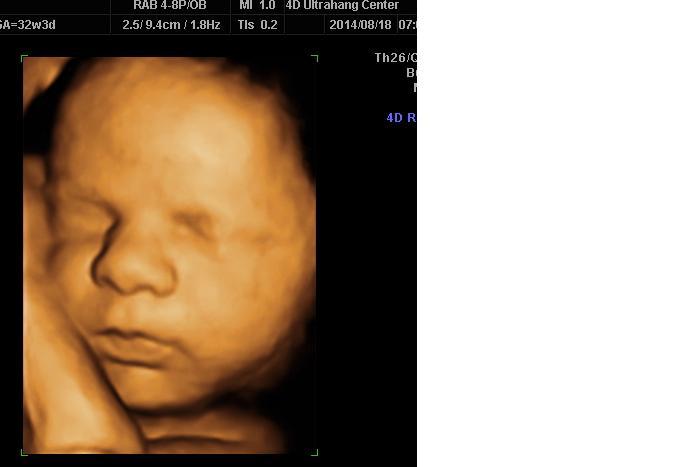

Kis Tündérkénk 27 hetesen és 1 naposan: